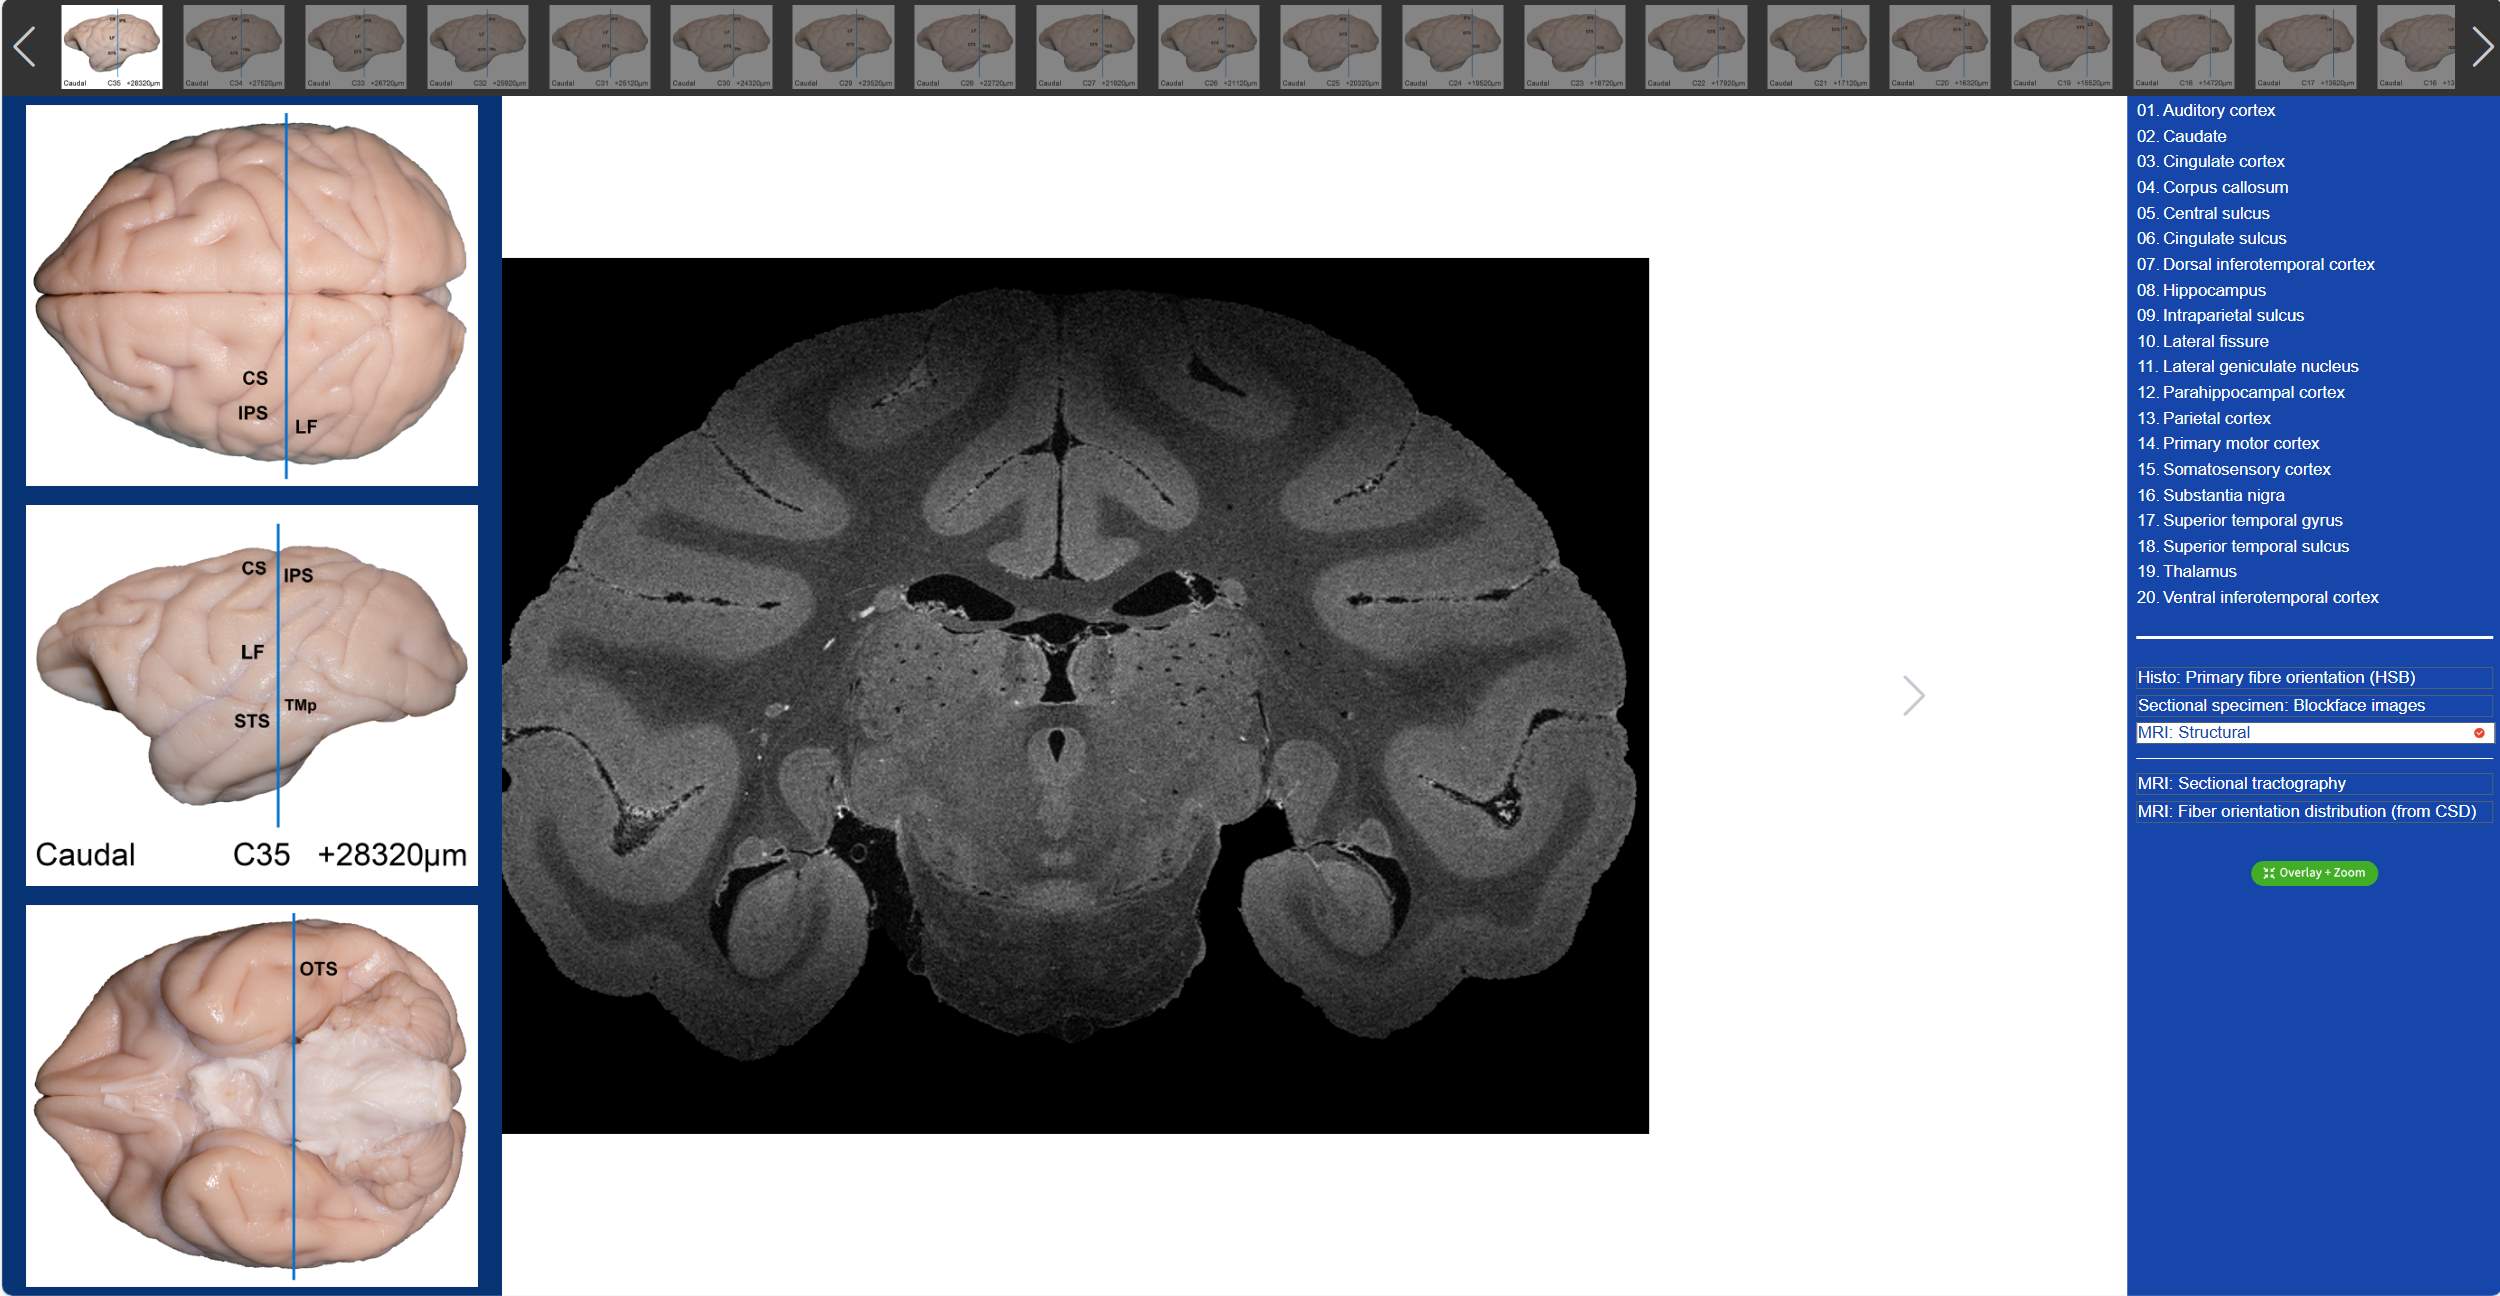

值得一提的是,在“動物腦樂園”里,不僅可以觀察到獼猴3D腦標本,還可以看到獼猴的全腦切片。吳勁松教授團隊從同一猴腦的離體MRI及全腦組織切片髓鞘染色(LFB)數(shù)據(jù)集中,間隔800μm取一層,構(gòu)建了集合組織切片髓鞘染色(LFB)、組織切片髓鞘染色-偽彩化、斷層標本圖、高分辨率MRI結(jié)構(gòu)像及離體腦dMRI斷層纖維束成像和纖維方向分布圖(限制球面反卷積-CSD)六大模態(tài)的斷層對照圖譜。我們只需要點擊相應的解剖名稱,就可以在圖譜上對應位置顯示標記,同時可與另外兩大模態(tài)的dMRI方向性信息進行對照,極大的方便了我們的觀看。